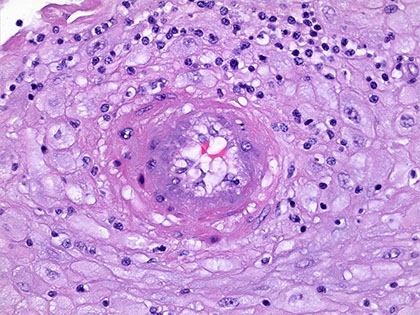

Chorangioma

most common type of placental neoplasm, with an

overall incidence of <1%. Typically, they are asymptomatic and are discovered incidentally at birth through gross examination of the placenta revealing a wellcircumscribed, spongy, red-brown nodule within the placental parenchyma, commonly at the periphery of the disc or directly below the cord insertion. Occasionally, multiple chorangiomas can be present. Most are discovered in mature placentas at 32-37 weeks’ gestation in mothers over the age of 30. Increasing maternal age has been correlated with increased incidence of chorangiomas. They are thought to develop as a reactive proliferation to hypoxia resulting in increased vascular endothelial growth factor production and angiogenesis. While most are incidentally found and have no clinical consequences, large chorangiomas (>4 cm)

may be associated with intrauterine growth restriction (IUGR), arterio-venous shunting, and fetal cardiac failure. Chorangiomas express GLUT1, similarly to

infantile hemangiomas, and may occur concurrently. While debated in the literature, some studies have shown a possible association between infantile hemangiomas and chorangiomas and even speculate that infantile hemangiomas may result from endothelial cell shedding from chorangiomas or hormonal influence during development.

Micro: well-circumscribed vascular proliferation composed of numerous capillaries. Examination of the nodule under high power reveals that the capillaries are surrounded by pericytes with no cytologic atypia. Mitotic figures are not readily identifiable. Surrounding the nodule, there are benignappearing cytotrophoblasts and syncytiotrophoblasts with appropriate syncytial knotting for gestational age. The few villi present surrounding the nodule are small,

mature, and appropriately developed for a third trimester placenta with a normal amount of vessels present